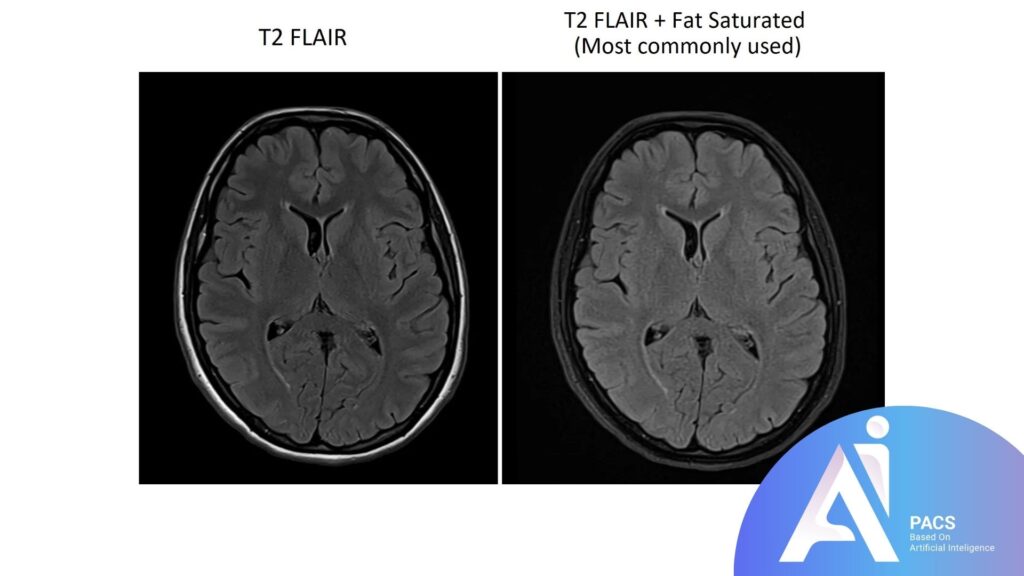

Comparison to other MRI sequences for context

Compared to standard T1 and T2 MRI sequences, FLAIR provides a unique advantage in brain imaging by isolating abnormalities near or within fluid-filled spaces. While T2-weighted imaging also highlights areas of high water content, the bright CSF can obscure details, especially near the brain’s ventricles. In contrast, FLAIR’s fluid suppression reveals subtle brain lesions, making it a crucial tool for diagnosing conditions like multiple sclerosis, stroke, and infections that might be harder to detect with other sequences.